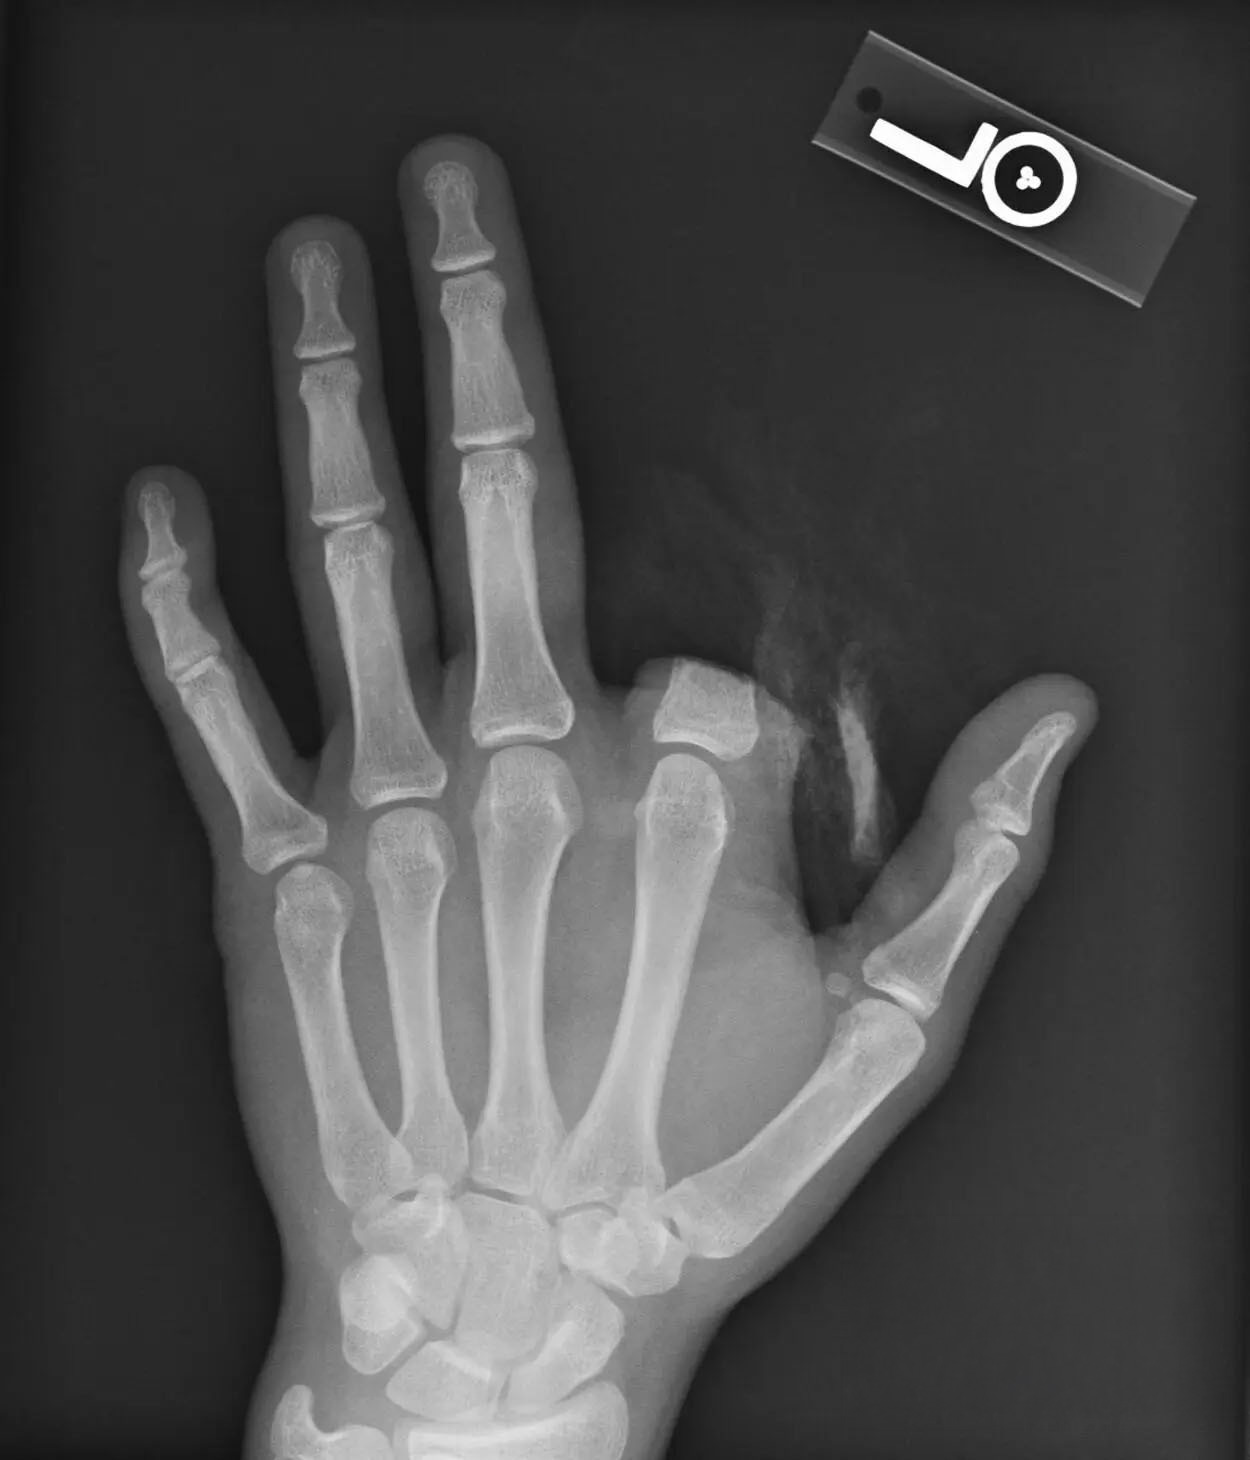

水槽の中のワニガメに触れようとした少年の指が噛みちぎられ、食べられてしまった画像。

医師たちは、食べられてしまった指を取り出して縫合しようとしたそうですが、それが成功したのかは不明とのこと。